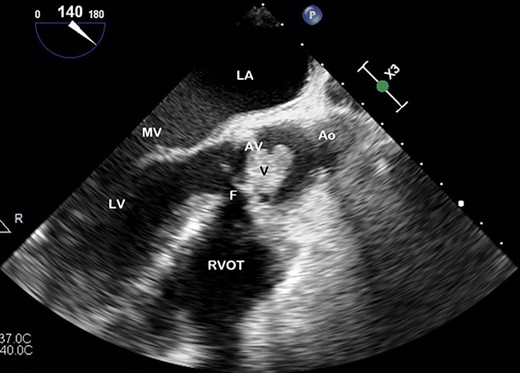

TOE, long axis demonstrating a vegetation (V) on the AV obstructing the left ventricular outflow tract; Ao, aorta; F, fistula; LV, left ventricle; MV, mitral valve.

Preoperative TOE, long axis with colour flow highlighting the vegetation (V) obstructing flow through the AV and the fistula (F) which has developed from left ventricular outflow tract to RVOT.